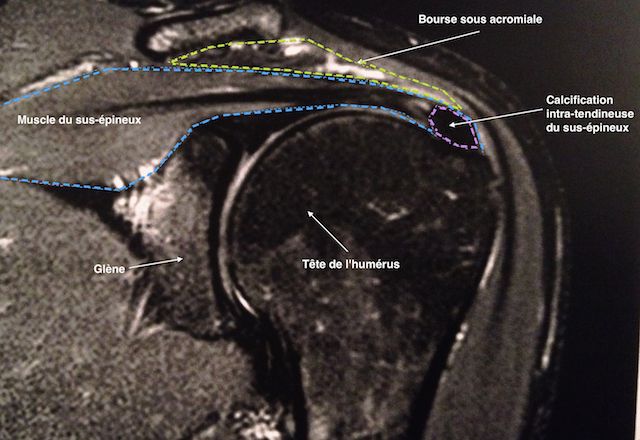

IRM d'une calcification du tendon du sus-épineux Figure 2 : IRM d'une calcification du tendon du sus-épineux

Puis, il pourra être utile de faire une IRM ou un arthroscanner, pour localiser la calcification et évaluer sa taille par rapport à l’épaisseur du tendon.